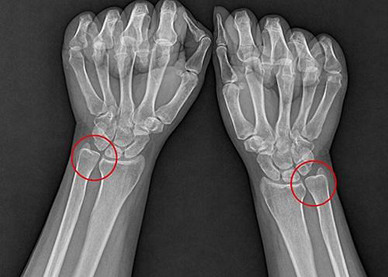

교정 전ㆍ척골 플러스 상태